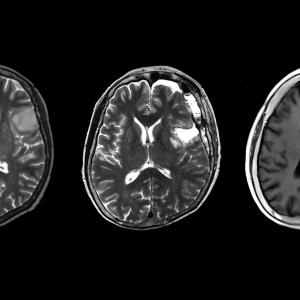

Възрастният мозък може да регенерира неврони в неочаквана област

За първи път учени откриха, че възрастните мозъци на мишки могат да произведат нови клетки в областта, наречена амигдала. Това откритие може да доведе до разработване на нови типове лечение на разстройства като тревожност и депресия, както и изобщо до по-добро разбиране на мозъка.

Амигдалата отговаря за широк спектър от емоционални реакции, и особено за тези, които са свързани със страха. Нарушените връзки в нея могат да доведат до тревожни разстройства, като например известното пост-травматично стресово разстройство.

Ако се потвърди окончателно, че мозъкът е способен да регенерира неврони в амигдалата, това ще означава, че учените могат да разработят принципно нови и перспективно успешни нови методи за справяне със тези разстройства.